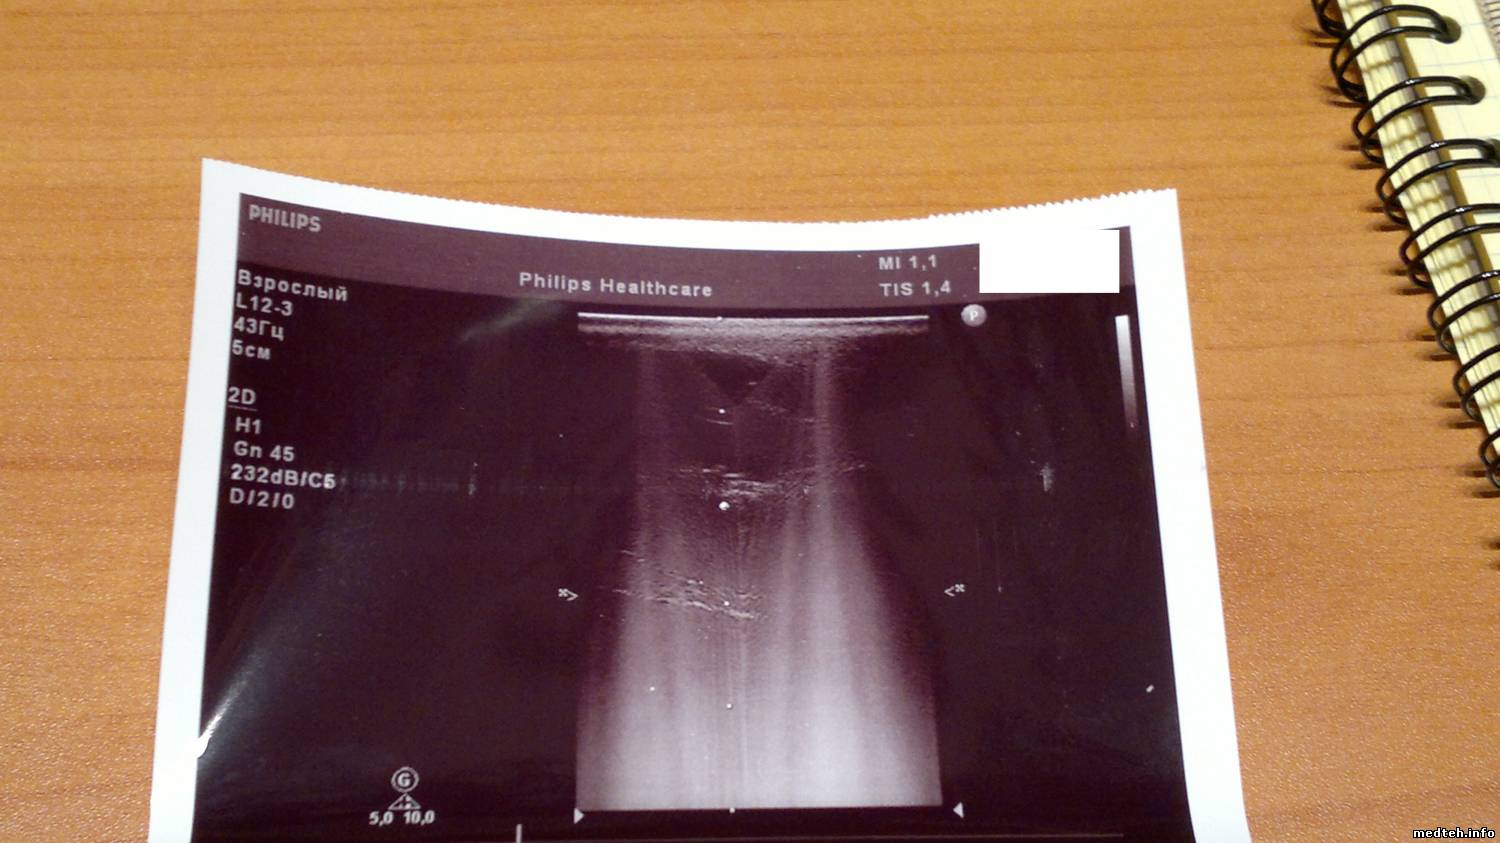

При тестировании аппарата выявились косяки с вагинальником и линекой-наложение серого фона/наводка(не знаю как обозвать), см. фото ниже.

Собственно нужно быть уверенным что дело в датчиках,а не в аппарате.Смущает симметричность наложиний серого на линейке. На вагинальнике нормально кажет только 1/5 часть всего сектора. Да, и к каждому датчику в упаковке шла распечатка с фантома-всё красиво и чётко. Вся упаковка цела, внешних/механических дефектов нет.

1367691.jpg (121.1 Kb) · 9129443.jpg (125.6 Kb) · 5411872.jpg (104.1 Kb)

А аксиомы Вы тоже проверяете? :) На последней картинке еще и по вертикали разделение или мне кажется?